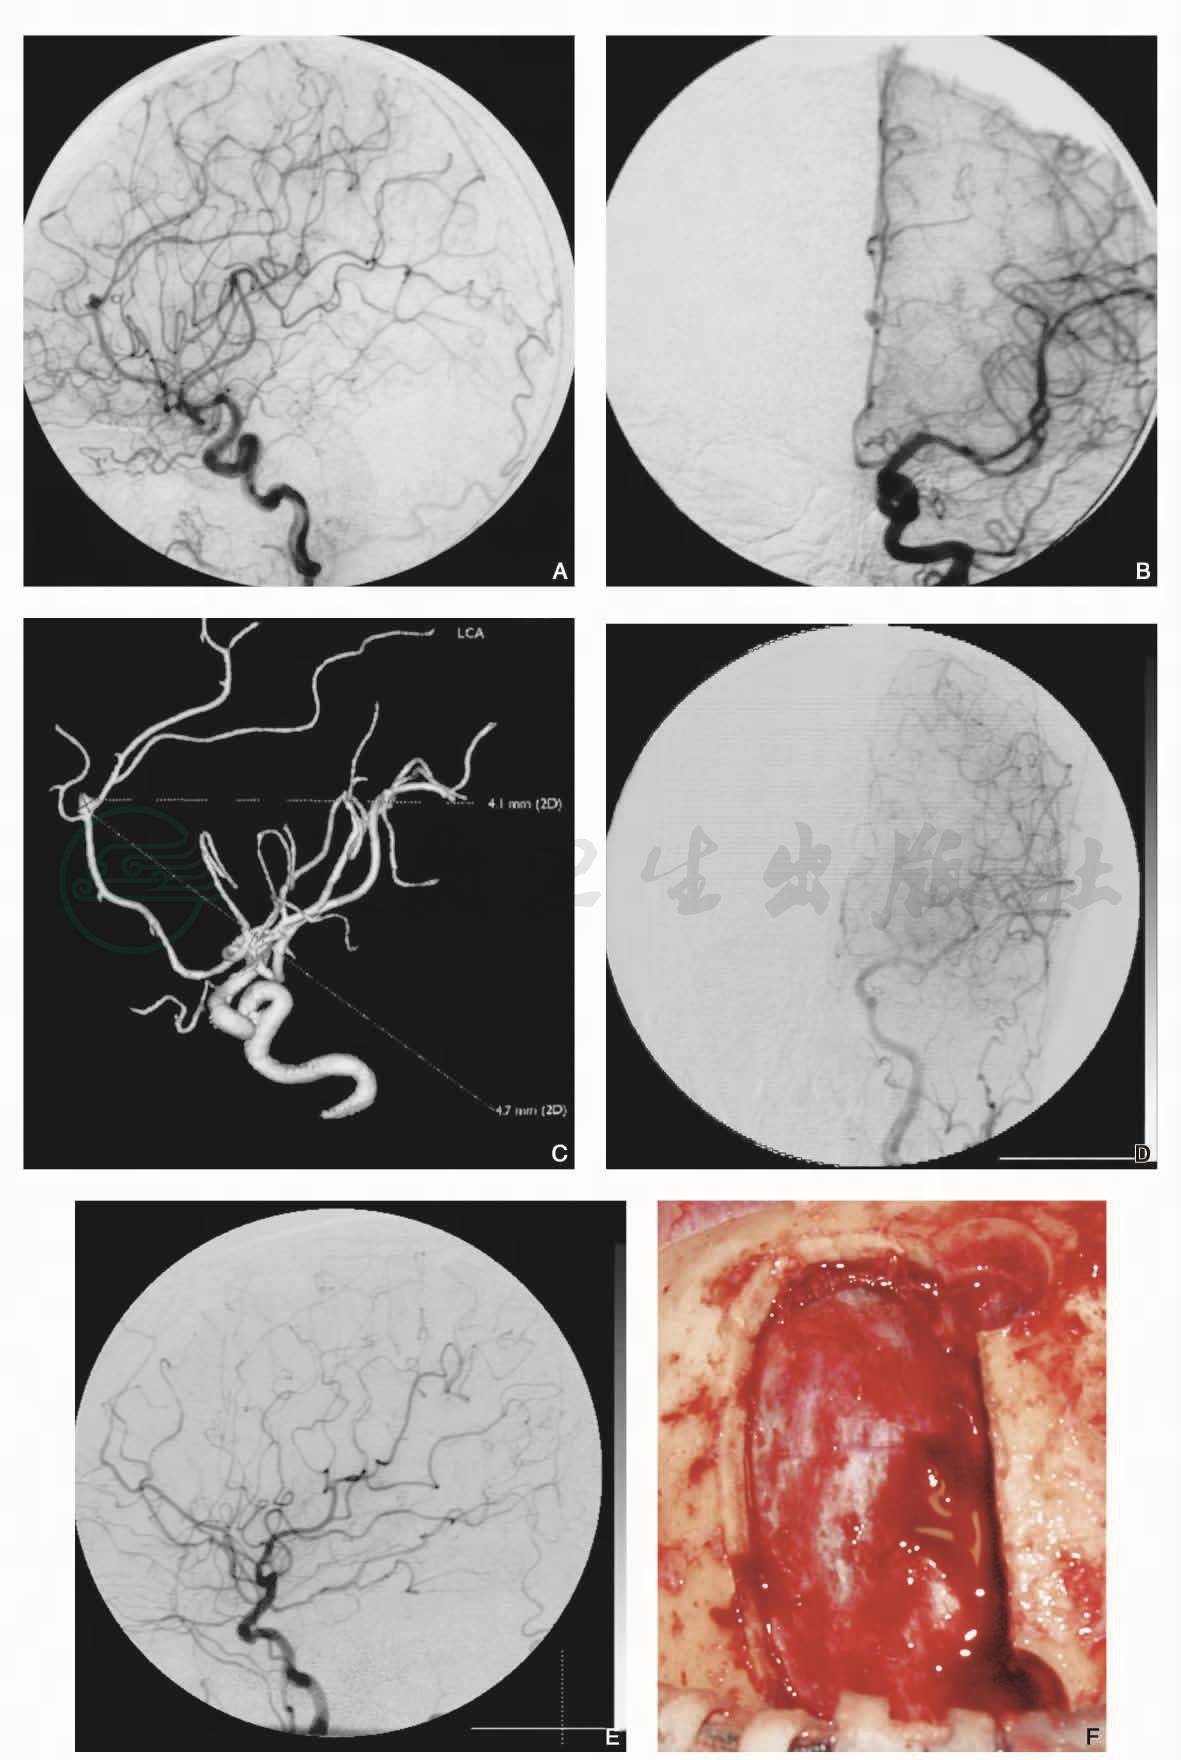

图6女性,64岁,左侧胼周动脉瘤

半球间入路夹闭。手术前左侧颈内动脉造影(DSA)显示胼周动脉瘤(A侧位,B正位),CTA(C)。手术后左侧颈内动脉造影(DSA)显示动脉瘤消失(DE)。左额半球间入路夹闭(FG),夹闭动脉瘤(H)。骨瓣复位固定(I)

引自:血管神经外科学(第2版).第2版.ISBN:978-7-117-37550-4.主编: